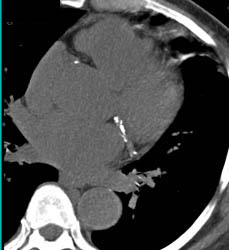

Enlarged Lv With Prior Infarct and Poor Wall Motion